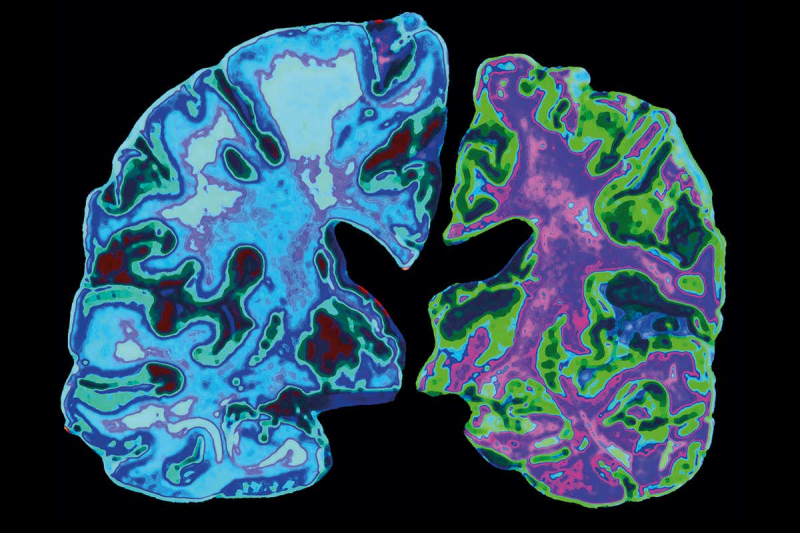

В обнаружении амилоидных бляшек помогли одноэнергетические рентгеновские снимки срезов мозга. В итоге удалось идентифицировать крошечные частицы меди и железа (около 1/10000 от размера булавочной головки) в ионизированной и элементарной формах, а также определить их степень окисления и составить карту распределения.

Изображения с рентгеновского микроскопа и спектры поглощения рентгеновских лучей. Снимки показали, что амилоидные бляшки содержат отложения как железа, так и меди / © Уорикский университет